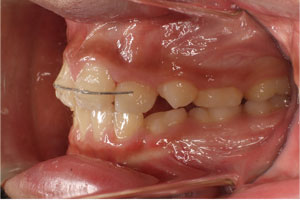

こちらの初診(男性)の患者さんは、開咬合 / 叢生歯列の症状がありました。

1期治療 8歳9ヶ月 2期治療 12歳4ヶ月から治療を開始し、1期治療 7ヶ月 2期治療 2年5ヶ月の間、スタンダードエッジワイズ法(与五沢エッジワイズシステム)を用い矯正治療を行いました。

| 症例分類 | 開咬合 / 叢生歯列 / 偏位咬合 | |||||||||||||||||||||||||||||||||||||||||||||||||||||||||||

| 動的治療期間 | 1期治療 7ヶ月 2期治療 2年5ヶ月 | |||||||||||||||||||||||||||||||||||||||||||||||||||||||||||

| 12歳4ヶ月 | 15歳8ヶ月 | |